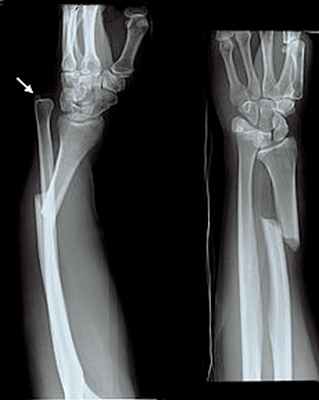

106. Переломы дистального отдела костей предплечья

Остеосинтез при переломах дистального отдела лучевой кости производят редко, как правило, при неудаче консервативного лечения. Для остеосинтеза применяют малую Т-образную пластину (Рис. 140).

Остеосинтез лучевой кости в дистальном отделе